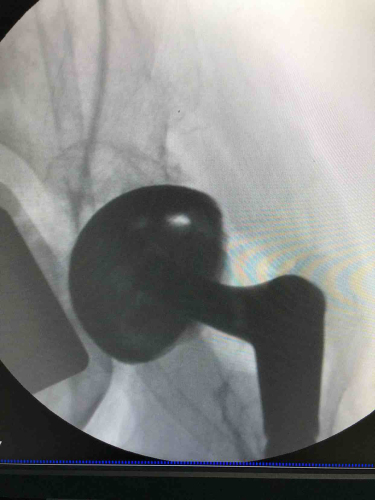

股骨头缺血性坏死 关节炎 四肢骨折 髋臼发育不良 髋关节疼痛 膝关节炎 肩袖撕裂 骨关节畸形 髋关节炎 关节骨折

擅长成人髋关节发育不良、股骨头坏死、强直性脊柱炎及类风湿关节炎疼痛畸形,以及髋膝关节、肩肘关节创伤、退行性骨关节炎等疾病的外科治疗,尤其擅长髋膝关节微创入路关节置换,复杂关节畸形首次置换以及膝髋关节翻修手术。

当股骨头缺血性坏死需要手术治疗,患者有时面临两种抉择。 展开>